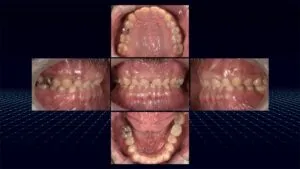

【症例のご紹介:前院で気になっていることを解決してもらえなかったと当院へのご来院】

今回ご紹介する患者さんは、元々、前歯の見た目を気にされており、その審美的な改善を希望して別の歯科医院にご相談されたという経緯をお持ちでした。ご自身の笑顔に自信を持ちたい、人前で口元を気にせず自然に笑いたいという切実な思いを抱えていらっしゃったのだと感じます。

しかし、残念ながら前院では、患者さんが最も気にされている前歯の問題に対して具体的な改善策が示されることなく、他の部分の治療が淡々と進められていったそうです。そしてご自身の悩みの核心に触れてもらえないまま時間だけが過ぎていく状況は、治療へのモチベーションを維持することも難しくなっていき、大きな不安と不信感につながったのだと思われます。

「必要な治療が沢山あるのかもしれないが、一番気になっていることが解決されないまま治療が進んでいき、最終的には自分が気になってることも解決されて自分のなりたい姿になれるのだろうか」

このような不安が募っていかれ、セカンドオピニオンを求めて当院の扉を叩いてくださいました。

▼実際の症例はこちらの投稿をご覧ください